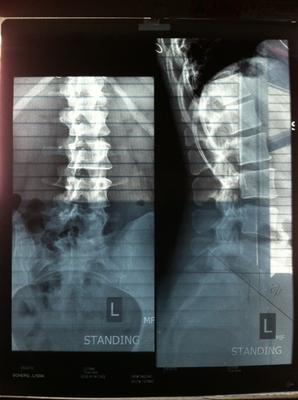

Pelvic XRay Standing

Here are the two X-Rays I have. They were taken back in the beginning of March of this year. Thank you for your time!

I take it you took these digi photos yourself of the original X-rays. Could you please take a spot picture of the right hip - get up close - and the lateral lumbo-sacral joint. These are not of diagnositic quality. Send them to brlewis@mweb.co.za without reducing the size of the images.

I can see there's something going on the right hip, but not what.

There is a huge amount of rotation of the lumbar vertebrae, so clearly this is a back and hip condition. Really two different conditions that feed off each other.